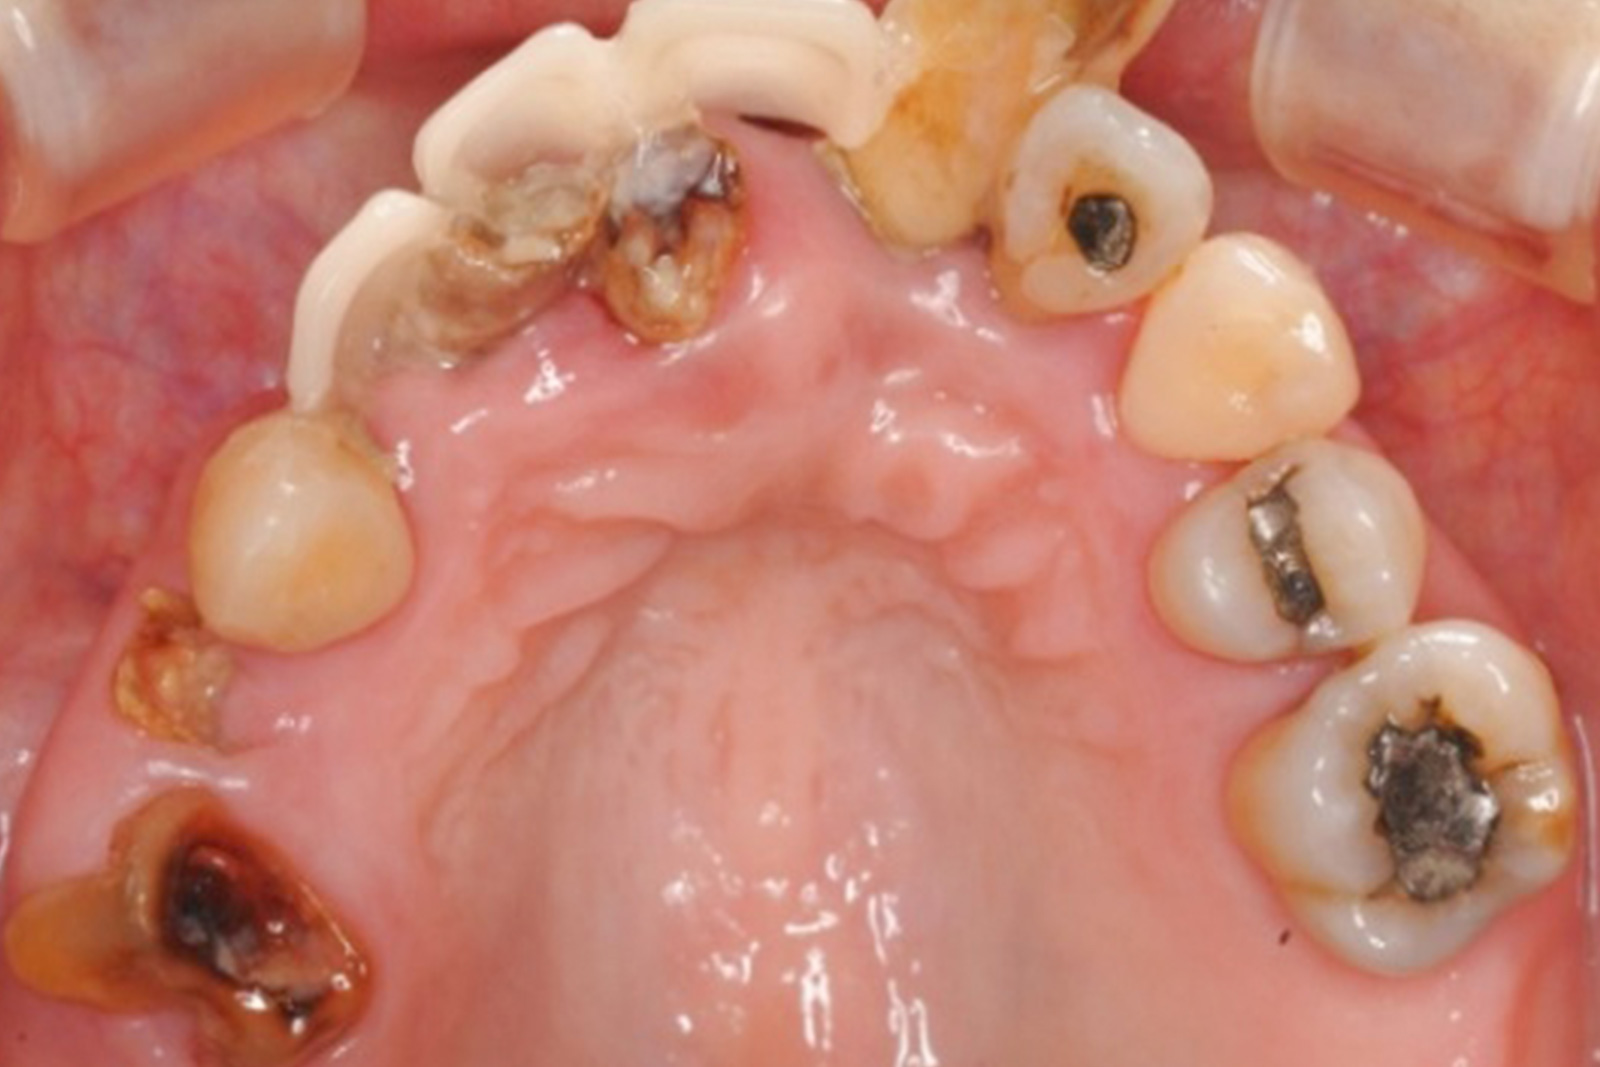

虫歯や歯周病を治療せずに放置していると、写真のように歯がボロボロの状態になってしまいます。

ここまで悪化すると、「もう、どうしようもない」と諦めてしまう方もいらっしゃいます。

歯科医療の進歩によって、ボロボロになった歯でも、歯の修復や機能の回復が可能になってきました。

当院がこれまで、どのような症例を手がけてきたのか。その一例を紹介します。

崩壊してしまった口の中の治療には、いくつかの方法がありますが、私はただ単に悪くなった歯を直し、機能が損なわれた歯を修復するだけではいけないと思っています。

大切なのは、どうして今のような状態になってしまったのか、原因を究明し、根本的な対策を講じることです。

それによって10年、20年後の歯の健康を見据えた精度の高い良質な治療が可能になるのです。